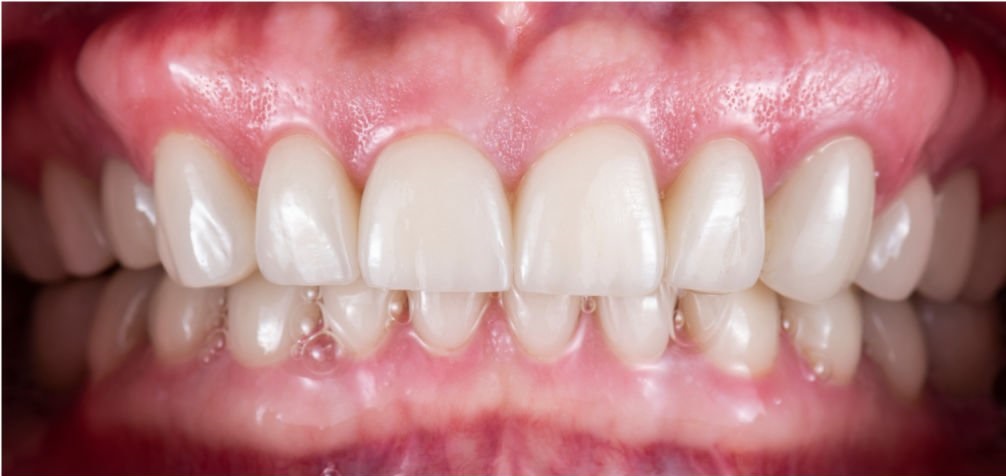

Протезирование

Проблема

Пациент обратился с жалобами на эстетическую неудовлетворенность передней группой зубов. Были изготовлены и установлены виниры E-MAX на передних зубах верхней и нижней челюсти.

Решение

Проделана следующая работа: установка керамических виниров повышенной эстетики E-MAX на передних зубах верхней и нижней челюсти.